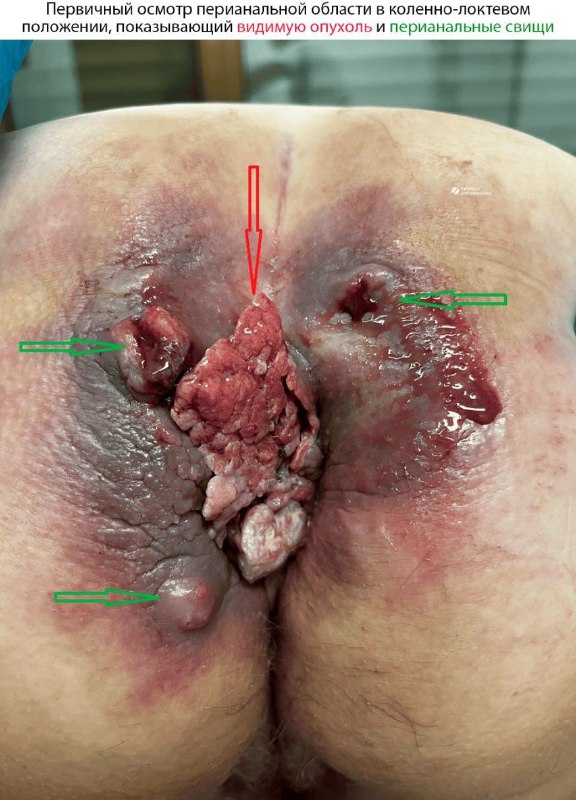

Наглядный пример опухоли Бушке-Левенштейна - плоскоклеточный рак, связанный с вирусом папилломы человека, вылеченный с помощью радикальной хирургии и химиотерапии:

2 мар. 2026 г.